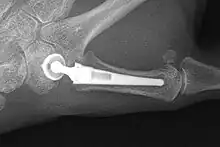

Joint replacement

The joint can be replaced with artificial material. An artificial joint is also referred to as a prosthesis. Prostheses are more problematic at the trapeziometacarpal joint compared joints like the knee or the hips.

[27]Prostheses come in many varieties, such as spacers or resurfacing prostheses.

It’s not clear within the current literature that a prosthesis has any advantage over trapeziectomy.[27]

Overall, joint replacements are related to long-term complications such as subluxation, fractures, synovitis (due to the material used) and nerve damaging.[35] In many cases revision surgery is needed to either remove or repair the prosthesis. Also note that usage of a joint replacement is heavy in costs.

The quality of the prostheses is improving and there is reason to believe this will have a positive effect on outcome in the years to follow.[27]